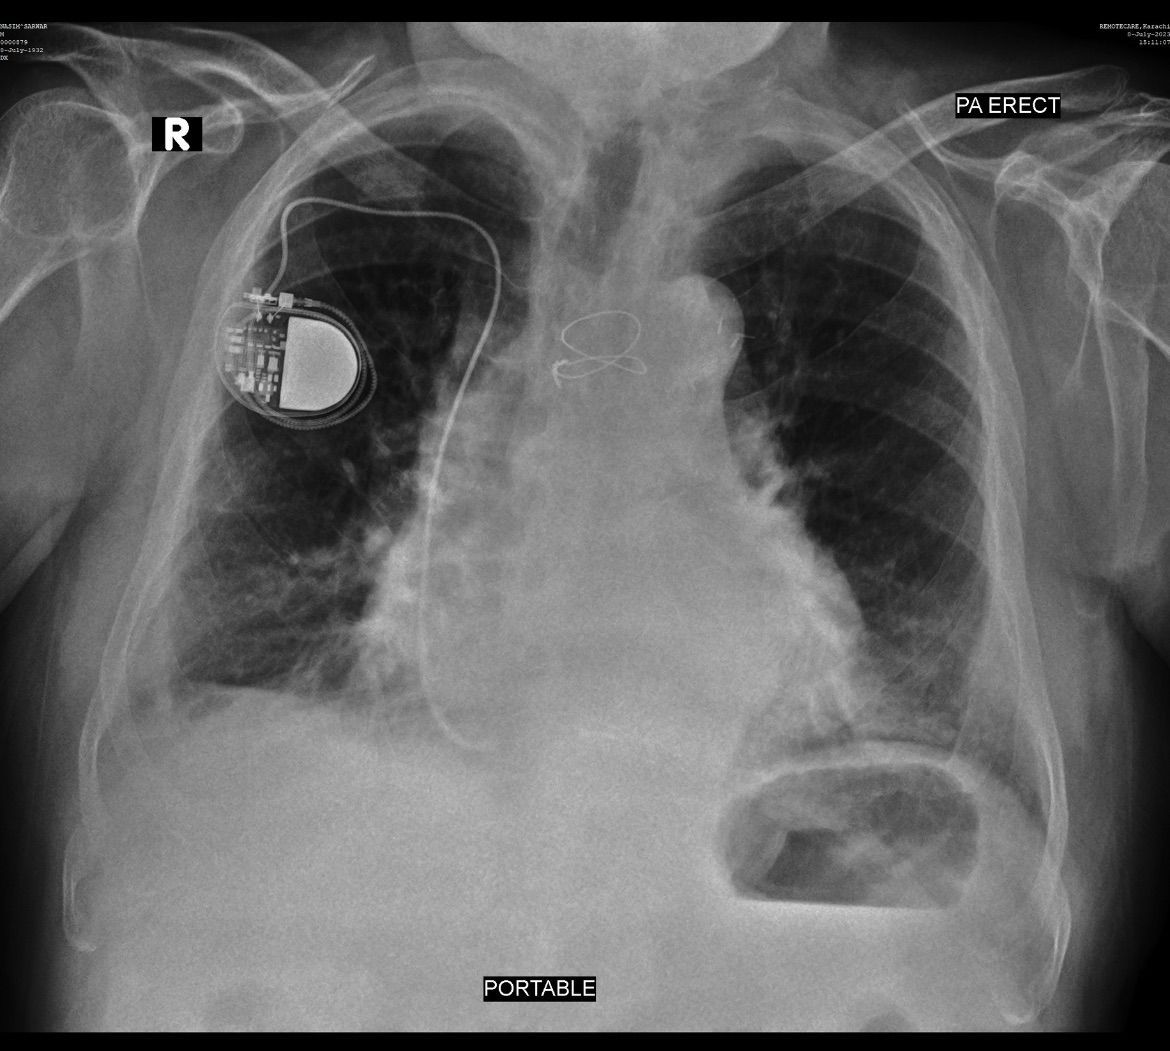

91 year old male, non-smoker known case of CHF with hx of pleural effusion 1 yr back, presented with chest congestion and productive cough (brown sputum) of 1 week. Treated as suspected case of pneumonia, given ceftriaxone 1g for 3 days. Sputum culture showed pseudomonas aeruginosa. Patient feeling better but cough not relieved. Following X-ray done after Antibiotic treatment, what should be the further plan of management. Other labs normal except hb 11, PLT 120 & 80% neutrophils.